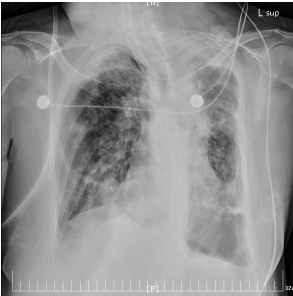

经以上综合治疗,患者病情逐渐好转,氧合较前改善,感染指标明显下降,肺部炎性渗出较前明显吸收;连续复查两次甲流核酸阴性,各脏器功能逐渐改善,尿量逐渐恢复,停止床旁血液净化治疗,目前CPAP模式持续脱机。

12月30日